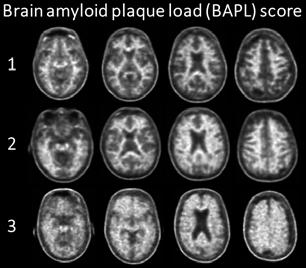

The activities of the MR Physics group are driven by clinical research lines of the Radiology and Nuclear Medicine department such as musculoskeletal research (with Edwin Oei), Lung MRI (with Harm Tiddens and Pier Luigi Ciet) and neuro-oncology (with Marion Smits). Besides the clinical research lines, it is important to notice that several fruitful projects are carried out on technical developments.